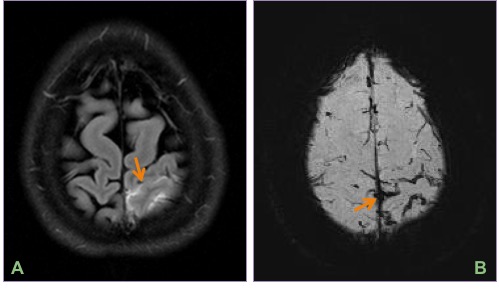

Axial FLAIR image (A) and minimum intensity projection (minIP) SWI image (B) showing minimal acute high parietal convexal subarachnoid hemorrhage.

MIP-MRA (A) showing diffuse beading of the A1 & M1 segments & distal branches. Based on the clinical presentation and imaging findings, a diagnosis of reversible cerebral vasoconstriction syndrome (RCVS) was suggested.